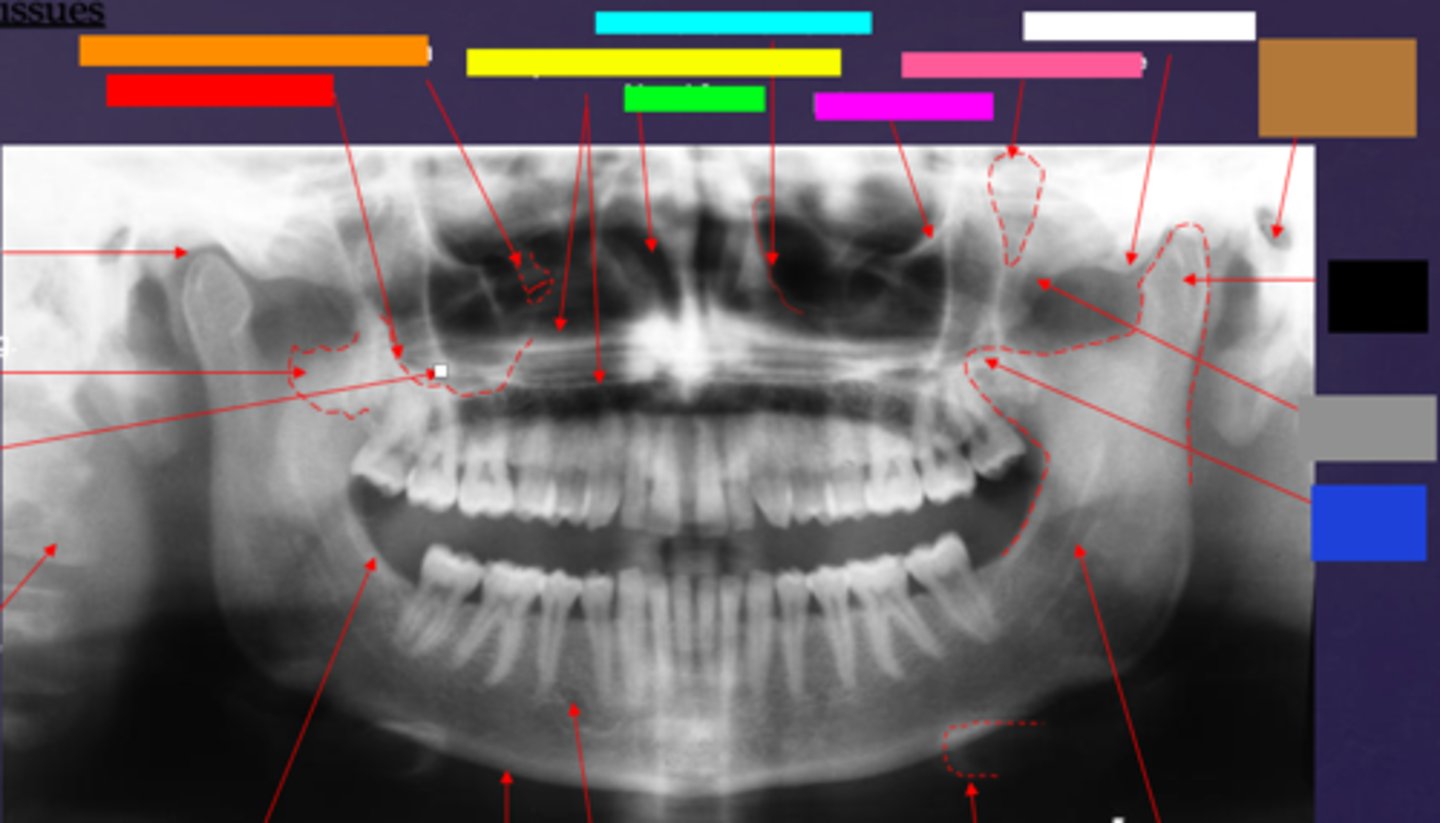

ID the soft tissue anatomy indicated by the arrow pointing from the red box:

posterior pharyngeal wall

ID the soft tissue anatomy indicated by the arrow pointing from the orange box:

soft palate

ID the soft tissue anatomy indicated by the arrow pointing from the yellow box:

dorsal surface of tongue

ID the soft tissue anatomy indicated by the arrow pointing from the green box:

middle nasal meatus

ID the soft tissue anatomy indicated by the arrow pointing from the light blue box:

inferior nasal meatus

ID the soft tissue anatomy indicated by the arrow pointing from the hot pink box:

inferior nasal concha (turbinate)

ID the soft tissue anatomy indicated by the arrow pointing from the brown box:

upper lip

ID the soft tissue anatomy indicated by the arrow pointing from the white box:

lower lip

ID the soft tissue anatomy indicated by the arrow pointing from the grey box:

ghost image of opposite mandible

ala of nose

nasal septum

columna (the septum separating the nostrils)

tragus

ear lobe